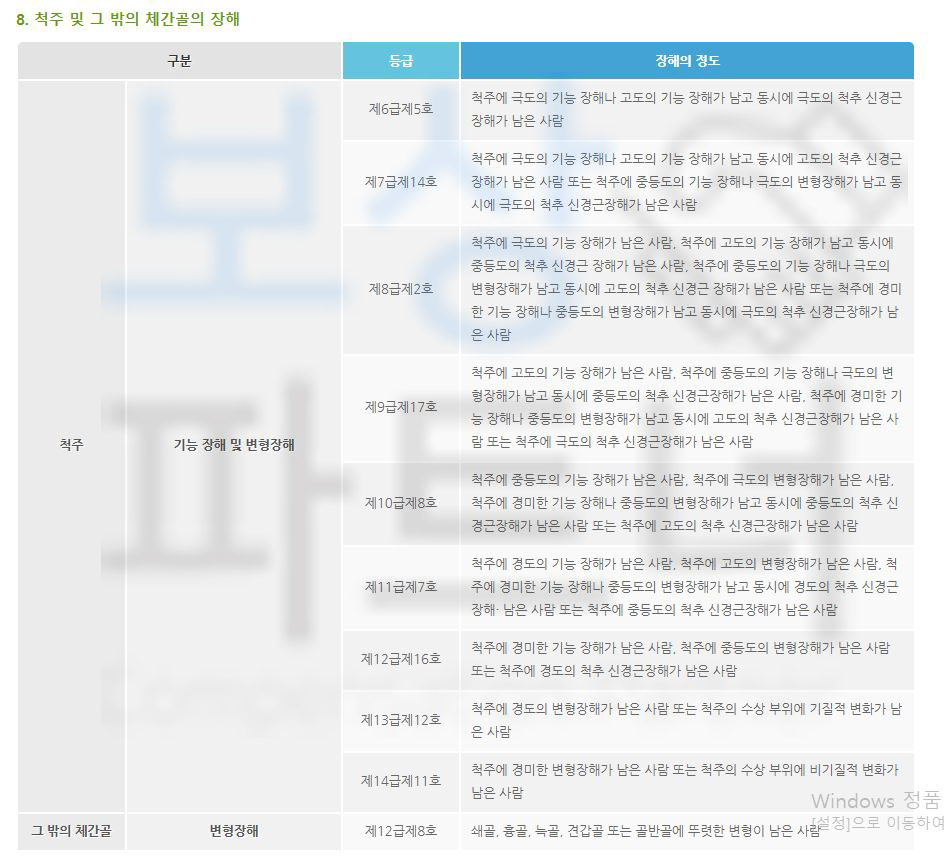

산재보험에서는 척추 골절을 아래와 같은 등급으로 보상 해주고 있습니다.